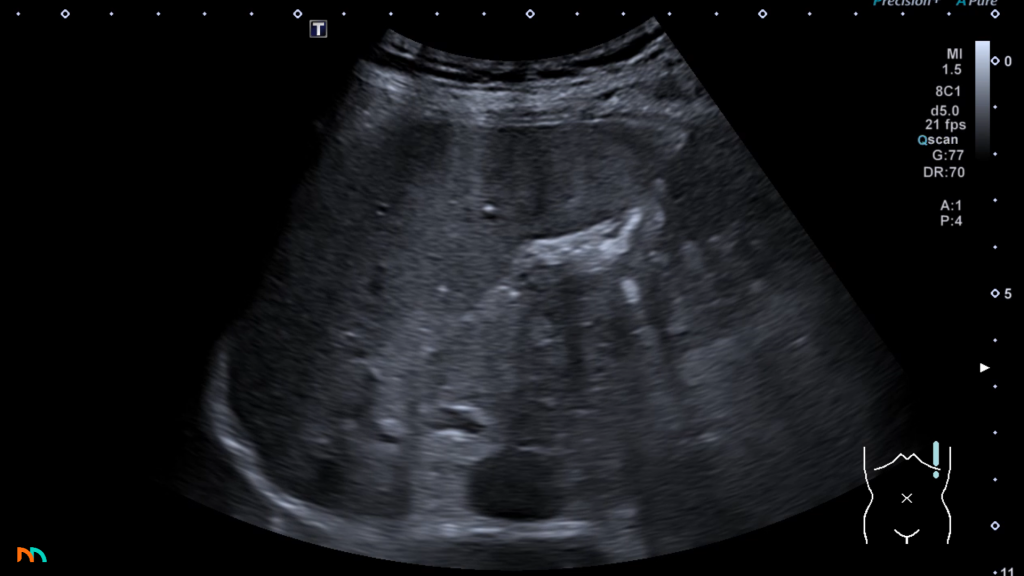

Po stronie lewej sytuacja jest nieco bardziej, z punktu widzenia ultrasonografii, złożona. Samo położenie pola nadnerczowego jest podobne jak po stronie prawej, szukamy go dogłowowo, do przodu i przyśrodkowo w stosunku do bieguna górnego nerki lewej. Niestety w tej lokalizacji nie mamy okna akustycznego w postaci wątroby, a żołądek oraz zagięcie śledzionowe okrężnicy, które często skutecznie ten obszar przesłaniają. Mimo to w badaniu nie powinniśmy pomijać tej okolicy. W związku z trudniejszymi warunkami insonacji stwierdzamy zmiany nadnercza lewego, dopiero gdy osiągną odpowiedni kaliber, w praktyce jest to średnica 20-30mm. Zdarza się, że zmian ogniskowych lewego nadnercza nie jesteśmy w stanie zobrazować, nawet wiedząc o ich obecności z innych badań obrazowych.

U szczupłych pacjentów możemy zlokalizować pole nadnerczowe nieco na lewo od aorty, umieszczając głowicę wysoko w nadbrzuszu, w okolicy wyrostka mieczykowatego